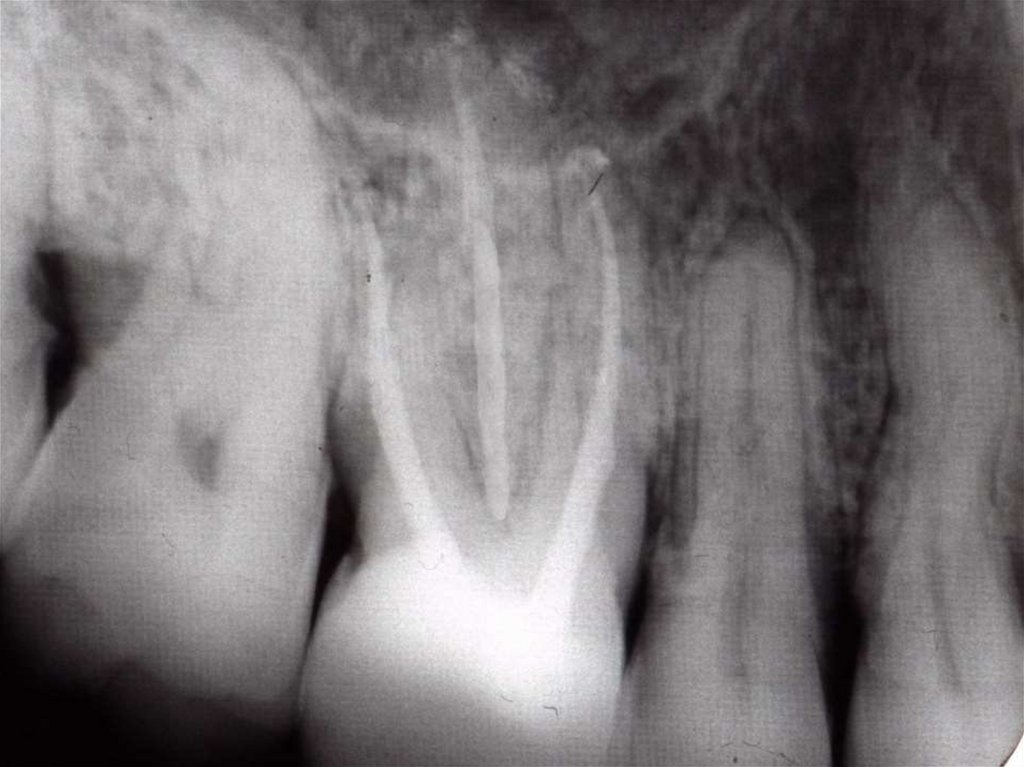

20. Раскрытая полость первых моляров

8. Рентген-контроль качества пломбирования